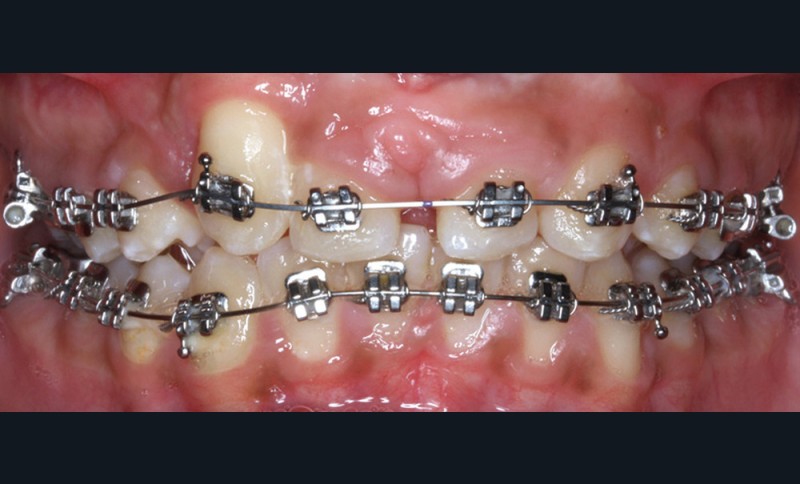

Antony, 11 ans se présente initialement pour une demande esthétique concernant ses deux incisives centrales qu’il trouve trop grosses (fig. 1a-c).

Le profil est convexe et associé à une inocclusion labiale au repos. Il s’agit d’une classe II squelettique sur un schéma facial normodivergent. Les rapports occlusaux sont de classe II bilatérale (complète au niveau molaire) avec des incisives inférieures vestibulo-versées. La 21 est géminée et la 11 vraisemblablement fusionnée avec un germe surnuméraire, sans altération de la formule dentaire. Du fait du diamètre mésiodistal fortement augmenté des incisives centrales, et du manque de place à l’arcade maxillaire qui en découle, les 12 et 22 sont en inversé d’occlusion en palato position. Les 53 et 63 sont persistantes sur l’arcade avec une inclusion en transposition incomplète de la 13, dont la cuspide se situe entre la racine de la 12 et celle de la 11 résorbée (fig. 1d-g).

Traitement multi-attaches

Dans un premier temps, l’extraction des 11 et 21 est réalisée. Un bouton est collé sur la 13, visible dans l’alvéole de la 11 afin de permettre sa désinclusion (fig. 2). La traction se fait à l’aide d’un arc TMA .016 x .022 en overlay afin d’avoir un axe de traction horizontal et vestibulaire évitant une résorption de la 12 à cette étape (fig. 3a,b) [3]. Ne pouvant pas mettre d’arc de Nance du fait de la position palatine des incisives latérales, il est convenu que des minivis d’ancrage peuvent être nécessaires si une perte d’ancrage postérieure est constatée (ce qui n’est pas le cas).